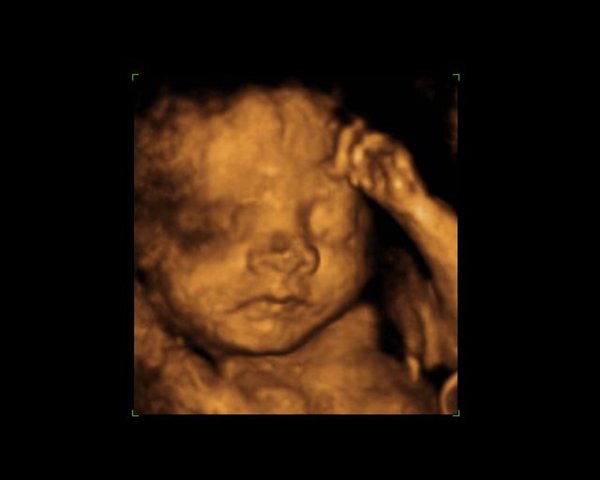

Dernæst havde vi bestilt tid til en privat 3d/4dscanning på scanningsklinikken i København, men den første gang lå hun med hænderne foran ansigtet, så vi blev tilbudt en ekstra gratis.. Det samme skete så anden gang igen og så var de så søde at vi fik en tredje gang, og så kunne vi endelig se hendes smukke ansigt